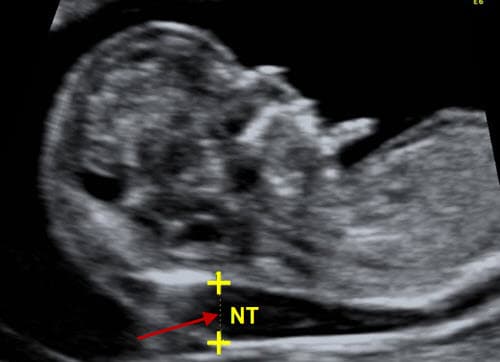

Khoảng sáng sau gáy là gì? xuất hiện từ tuần thứ 11 đến 13

Khoảng sáng sau gáy của thai nhi là độ mờ của vùng da sau gáy, xuất hiện từ tuần thứ 11 đến 13 của thai kỳ. Đo khoảng sáng sau gáy là một trong những phương pháp giúp xác định khả năng mắc hội chứng Down ở trẻ. Khoảng sáng sau gáy là gì? Khoảng […]